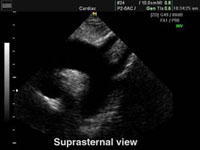

SUPRA-STERNAL View

S Suprasternal View

• Ascending Aorta.

• Aortic Arch.

• Branches of Aortic Arch.

• Upper part of Descending Aorta.

• Pulmonary Artery and branches.

DiDiagnostic for:

• PDA

• Ao.Co arctation.

• Ao. Aneurysm (& dissection).

• Others.